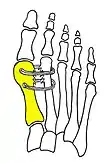

Cerclage bone sutures

Fig. 2: Cerclage bone sutures

Fibrous connecting bridge to prevent recurrence

Fig. 3: Fibrous connecting bridge to prevent recurrence

Syndesmosis procedure addresses specifically the two fundamental problems of metatarsus primus varus deformity that gives rise to the bunion deformity. They are leaning and instability of the first metatarsal bone . Syndesmosis procedure uprights the leaning first metatarsal bone with strong binding sutures between it and the second metatarsal bone (Fig. 2) and then also stabilizes it uniquely by creating a fibrous connecting bridge between these two bones (Fig. 3, 4). First metatarsal bone can be readily realigned because by definition of the metatarsus primus varus deformity its first metatarsal is abnormally loose and mobile.